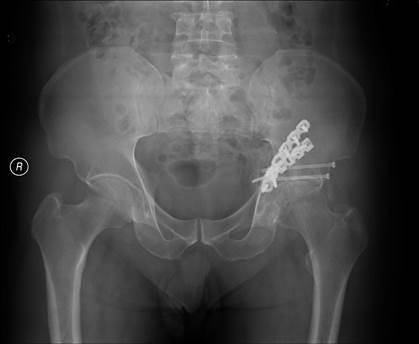

病例一:左髋臼骨折、骶髂关节脱位,Tile C3分型,术后复查X线